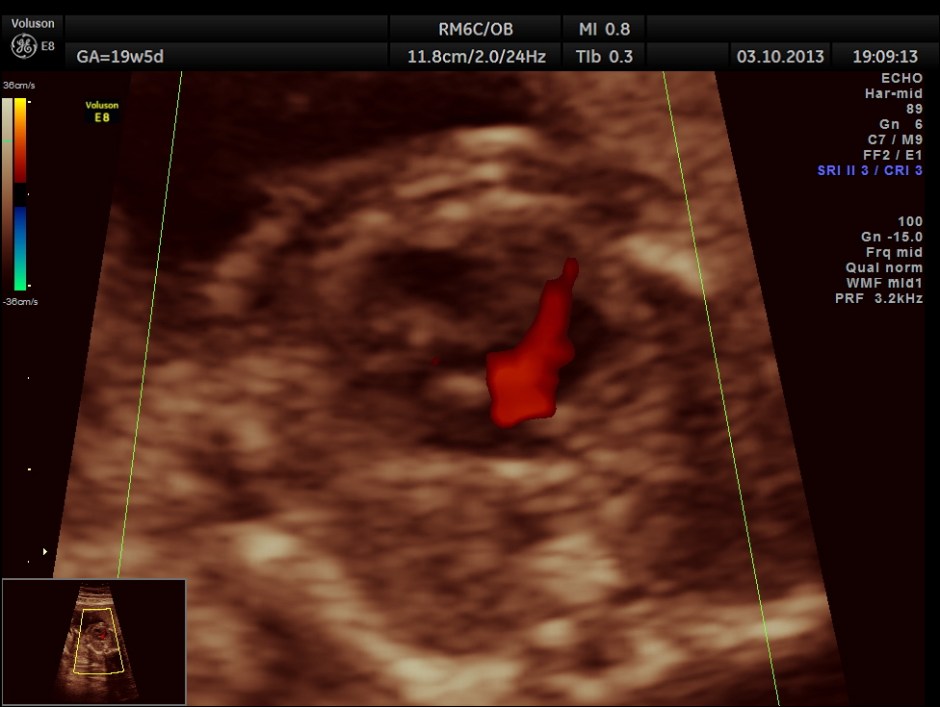

Colour flow also rules out the possibility of hypoplastic left heart syndrome.

Aortic arch is progressively narrowed with the isthmus appearing very narrow. A flow reversal is also seen .

The following picture shows the reversal of flow in the foramen ovale , which according to some authors is a salient diagnostic feature of co-arctation of aorta.

The diagnosis offered was PROBABLE CO-ARCTATION OF AORTA .